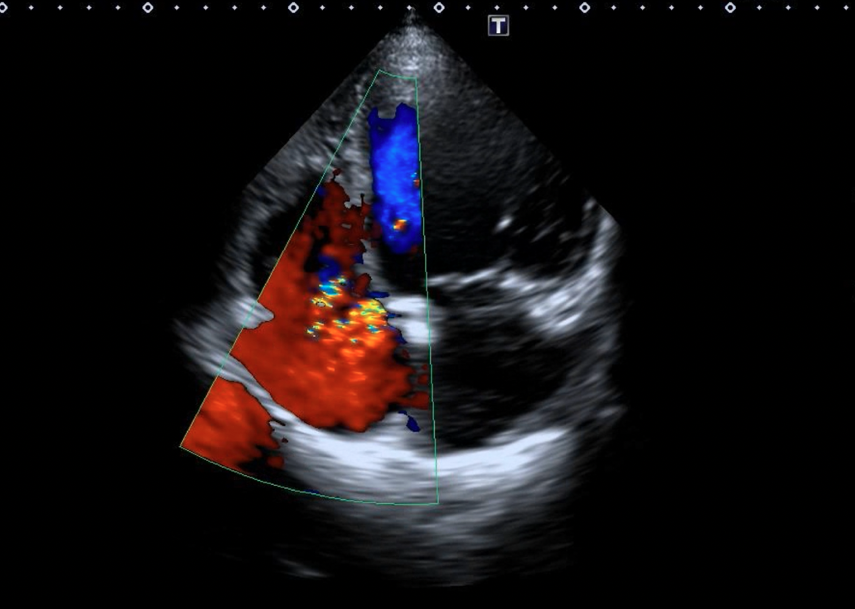

Based on the diagnosis of acute heart failure, the patient was admitted and her treatment was optimized, with an echocardiogram following, which showed:

• Annular dilatation of the mitral valve with anterior mitral leaflet prolapse;

• Eccentric jet of mitral regurgitation;

• Sclerotic aortic valve with grade II calcification;

• Pressure gradient = 22 mmHg, annulus = 18 mm, sinus of Valsalva = 23 mm;

• Rupture of sinus of Valsalva communicating with the right atrium with continuous flow on continuous wave Doppler.

Figure 4. (A) Positioning of the Amplatzer Duct Occluder (ADO) device (Abbott) (blue arrow). (B) Transthoracic echocardiography. (C) No residual shunt observed across the defect following device placement on transthoracic echocardiography.

(Figure 4B)